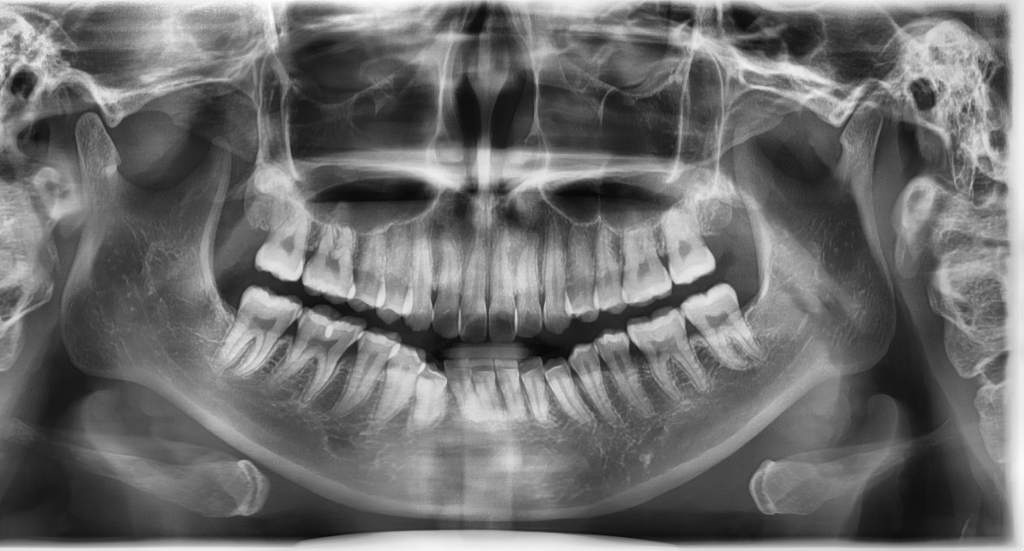

열흘 전에 다른 치과에서 찍은 엑스레이인데 별 다른 이상은 없다고 하셨는데, 제 윗앞니 뿌리가 많이 짧은 편인가요?? 걱정돼서요 ㅠ

1. 치아 뿌리의 경우 유전적으로 짧은 경우도 있고 교정치료를 해서 짧아지는 케이스도 있습니다. 위 방사선 사진만 보고는 아래 앞니 뿌리가 원래 짧은 것인지 아니면 아래 앞니가 앞으로 기울어져서 (flaring) 사진 상 왜곡된 것인지 알 수는 없습니다. 혹시 본인 아래 앞니가 앞으로 기울어져 있지는 않은지 확인해보시기 바랍니다. 만약 그렇다면 실제 치근 길이는 정상이어도 사진으로는 저렇게 짧게 나오는 경우도 있습니다.